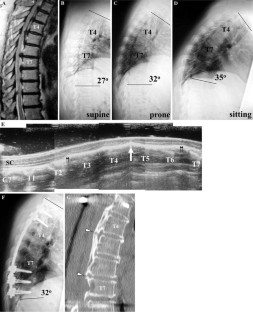

Fig. 1